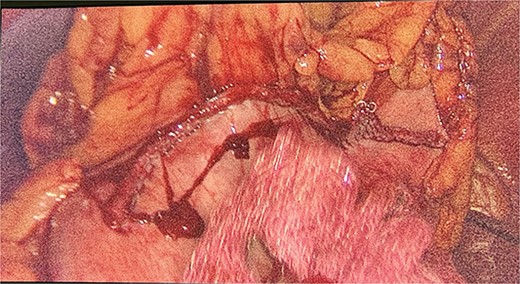

We had to first liberate the adhesions of the colon from a previous operation before gaining entry to the left colon. To do so, we made an incision in the White line of Toldt and dissected the right gastrocolic and splenocholic ligaments. This allowed us to access the retrocolic space and approach the left kidney. We identified the left renal vein and the left suprarenal gland and dissected the gland from the fatty tissue of the kidney. The gastrosplenic ligament was also liberated through the ligation of short gastric arteries. After separating the stomach from the posterior abdominal wall, we located the GIST (Fig. 3) on the posterior part of the fundus and removed it through wedge resection (Fig. 4).

After the surgery, she was closely monitored for any possible complications. There were no signs of intra-abdominal bleeding, high blood pressure, intra-abdominal infection, abscess, or delayed wound healing. As a result, the patient was discharged from the hospital on the 14th day following the surgery. During the follow-up, the patient had her blood pressure and hormone levels normalized. The follow-up results showed that the aldosterone at rest was 14.2 ng/dL. She also reported withdrawal of headaches and stomach pains. The pathological result came in as micro- and macronodular hyperplasia of the left suprarenal gland and GIST with a very low risk of progression.